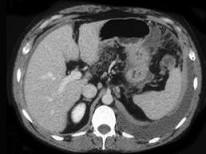

问题 女,36岁,低热、乏力,腹胀不适1月余,结合影像检查,应考虑为 ( )

选项 A.肝硬化腹水 B.结核性腹膜炎 C.腹腔转移瘤 D.心源性腹腔积液 E.急性化脓性腹膜炎

答案 B